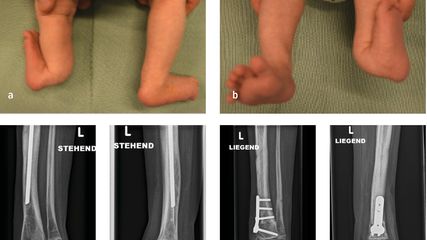

Angeborene Fehlstellungen des Unterschenkels

Kongenitale Deformitäten des Unterschenkels gehören zu den seltenen, aber medizinisch bedeutenden und operativ herausfordernden Diagnosen der Kinderorthopädie. Eine differenzierte ...